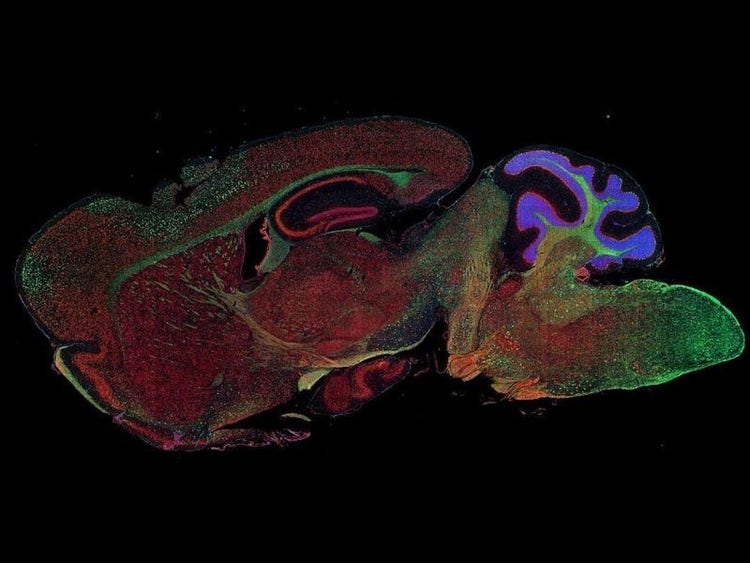

Fluorescence imaging of a mouse brain

Jedes dieser Bilder sieht aus der Nähe anders aus, aber sie fügen sich zu einem Bild eines Mäusegehirns zusammen, das mit Fluoreszenzbildgebung aufgenommen wurde.

Der britische Wissenschaftler Sir George G. Stokes beobachtete zum ersten Mal, dass das Mineral Flussspat fluoresziert, wenn es mit ultraviolettem Licht beleuchtet wird, und prägte den Begriff „Fluoreszenz“. Stokes fand heraus, dass das fluoreszierende Licht eine größere Wellenlänge hat als das Anregungslicht, ein Phänomen, das heute als Stokes-Verschiebung bekannt ist. Die Fluoreszenzmikroskopie ist eine hervorragende Methode zur Untersuchung von Materialien, die entweder in ihrer natürlichen Form (Primär- oder Autofluoreszenz) oder nach Behandlung mit fluoreszierenden Chemikalien (Sekundärfluoreszenz) fluoreszieren können.